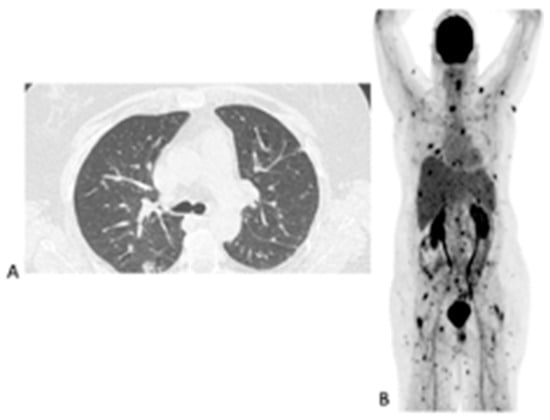

We included 155 [18F]FDG PET/CT studies from 73 patients who were diagnosed with IFIs. The majority of the patients (n = 49, 67%) were males, and the median age at the time of the scan was 56 years, with a range from 9 months to 76 years. Fifty-nine (81%) patients were from UMCG, and fourteen (19%) were from UMCU. Forty-one patients had a single [18F]FDG PET/CT in the assessment of IFIs. The IFIs were classified according to the revised EORTC/MSG criteria, and the results are displayed in Table 1. Thirty-two patients had repeated [18F]FDG PET/CT studies performed to monitor the responses (Table 2). Fourteen (45.1%) of the patients who had repeated [18F]FDG-PET to monitor the treatment of the IFIs did not have proven IFIs as per the EORTC/MSG criteria. The conditions underlying the IFIs are tabulated in Table 1. There were five major indications for [18F]FDG PET/CT study. These five indications are displayed in Table 2 below. Figure 1 shows the initial chest X-ray, HR CT and fused axial [18F] FDG PET/CT through the chest of a patient with a proven fungal infection and the follow up [18F]FDG PET/CT study.

Figure 1. Chest X-ray, HR CT and [18F]FDG PET/CT of a 60-year-old female with acute myeloid leukemia on chemotherapy. She had a proven fungal infection (Alternaria alternata). (A)—Initial chest X-ray. (B)—Initial HR CT scan performed before the [18F]FDG PET/CT. (C)—Fused axial image of [18F]FDG PET/CT of the chest. After 2 months of antifungal therapy. (D)—Chest X-ray showing response with a residual lesion. (E)—Fused axial [18F]FDG PET/CT showing an almost complete metabolic response in the IFI lesion. The data provided by [18F]FDG PET/CT at follow-up were deemed adequate, so patient did not require a repeat HR CT.